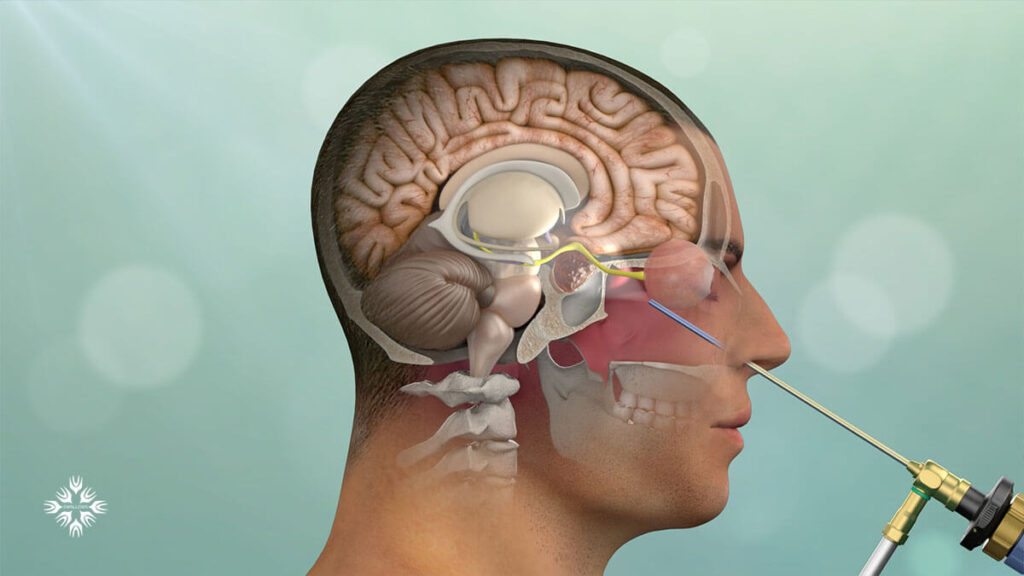

قیمت: 68٬000 تومان - دسته بندی فایل: پاورپوینتپاورپوینت مایع مغزی نخاعی (CSF)

فروش ویژه پاور پوینت حرفه ای مایع مغزی نخاعی (CSF) با تخفیف استثنایی فقط 103 هزار تومان تعداد اسلاید: 66 اسلاید